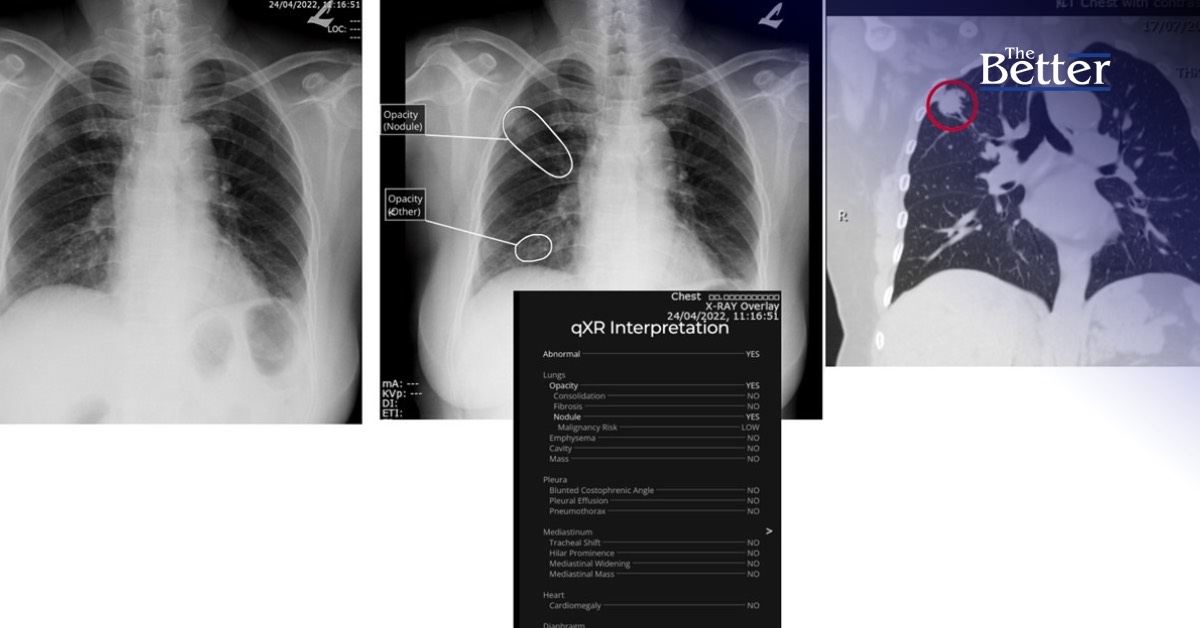

ทั้งนี้ ด้วยความก้าวหน้าของเทคโนโลยีดิจิทัลในปัจจุบัน ทำให้มีการนำเทคโนโลยี AI เข้ามาช่วยเพิ่มประสิทธิภาพและขีดความสามารถของการตรวจเอกซเรย์คอมพิวเตอร์ช่องอก เพื่อตรวจหาก้อนเนื้อในปอดซึ่งอาจเป็นตัวบ่งชี้มะเร็งปอดในระยะเริ่มต้นที่อาจมีขนาดเล็กหรือมองเห็นได้ยากภายในระยะเวลาเพียง 3 นาที ร่วมไปกับการตรวจสอบยืนยันผลจากรังสีแพทย์ เพื่อให้ได้ผลการตรวจที่แม่นยำที่สุด

ซึ่งที่ผ่านมา ได้มีการใช้เทคโนโลยี AI เพื่อตรวจหามะเร็งปอดเบื้องต้น และโรคอื่นๆ ในปอดให้กับโรงพยาบาลพระปกเกล้าและโรงพยาบาลโป่งน้ำร้อนแล้วกว่าพันราย ในจำนวนดังกล่าว มีผู้ตรวจพบรอยโรคที่สงสัยก้อนเนื้อในปอด มากกว่า 50% และพบรอยโรคที่สงสัยก้อนเนื้อในปอดที่มีโอกาสความน่าจะเป็นในการเป็นโรคมะเร็งปอดสูงถึง 0.8%